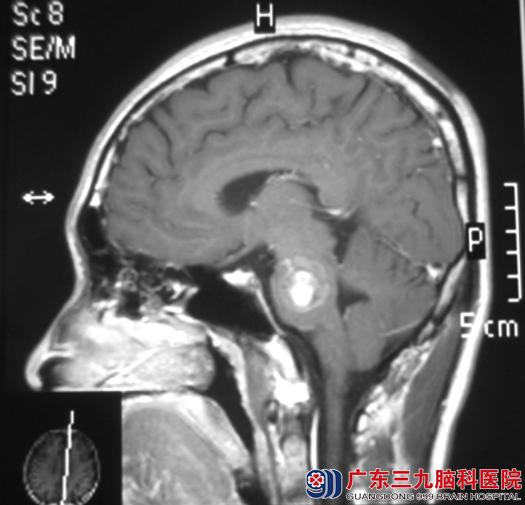

覃先生30岁,1月前出现右侧肢体乏力。当地医院行头颅MRI检查发现:脑干处有一高低信号的低密度影,考虑海绵状血管瘤。

广东三九脑科医院MR显示:桥脑偏左侧有一类圆形病灶,大小为20mm×19mm×26mm。综合神经外科鲁明主任告诉他们:脑干是海绵状血管瘤的相对好发部位,尤以桥脑比例最高。脑干海绵状血管瘤属于血管性病变,较其他部位海绵状血管瘤更容易发生瘤内出血,肿瘤的大小会根据血管破裂出血而逐渐增大,如果不及时手术切除很有可能影响到患者的生命。

手术前